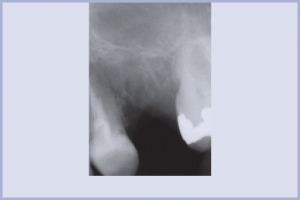

- Fig. 21 – RX pre-intervento

La radice del 2.5 deve essere estratta per frattura corono-radicolare complicata (Figg. 21-23).

Il difetto osseo è colmato con il riempitivo MBCPTM Putty (Fig. 24); anche qui viene eseguita una radiografia in seduta (Fig. 25) e un controllo a 1 mese e 3 mesi di distanza (Figg. 26, 27). A 6 mesi una TC evidenzia un ottimo mantenimento dell’osso alveolare nella sede della rigenerazione (Fig. 28) con scarso sviluppo in senso corono-apicale. Si inserisce un impianto Max Stability di 4,5 mm di diametro e 12 mm di lunghezza con tecnica flapless e mini rialzo del seno mascellare effettuato con tecnica osteotomica (Figg. 29-32) e si posiziona un tappo basso con connessione conica (Fig. 33). Dopo 5 mesi (Fig. 34) si finalizza il lavoro con il posizionamento di una corona in metallo-ceramica (Figg. 35-37).